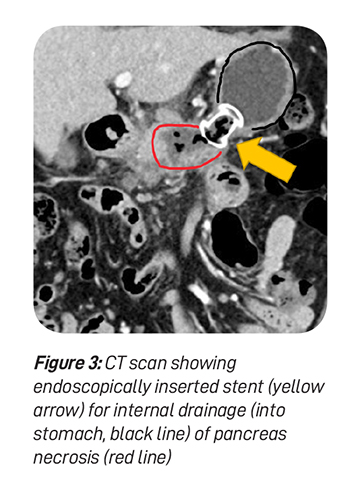

The pseudocyst requires drainage of fluid contents. The contents are typically drained internally into adjacent organs like the stomach or small intestine. The drainage procedure can be done by endoscopy (see figure 3) or surgery. Surgery can be either performed by open wound or keyholes. Pseudocysts develop more commonly following chronic pancreatitis.